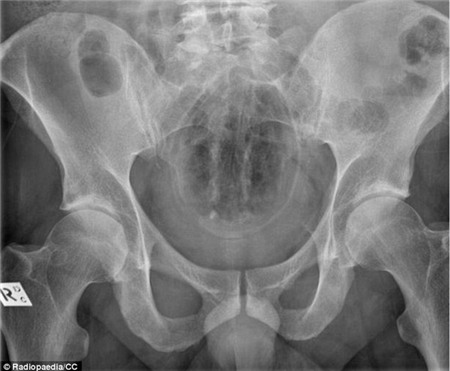

Đây

là hình chụp X-quang của một người đàn ông 40 tuổi. Trong trực tràng

của là một cái chày cán. Ông nói rằng mình trượt tay khi đang nấu món ăn

Malaysia khiến nó rơi vào trong trực tràng.